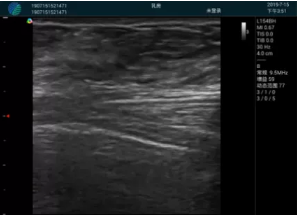

可視化穿刺引導(dǎo)

M20實(shí)時(shí)引導(dǎo):向包塊后方間隙注射利多卡因

清晰顯示腺體內(nèi)低回聲快影,邊界清晰,包膜較光滑

確定進(jìn)針路徑并實(shí)時(shí)監(jiān)測抽吸針與腫塊位置關(guān)系

抽吸針進(jìn)入腫塊內(nèi)部進(jìn)行旋切

抽吸過程中可見腫塊明顯縮小,并根據(jù)腫塊位置改變針道位置

抽吸旋切后再進(jìn)行超聲復(fù)查,原腫塊區(qū)域未見殘留組織及出血

超聲引導(dǎo)下抽吸旋切取出的腫塊組織